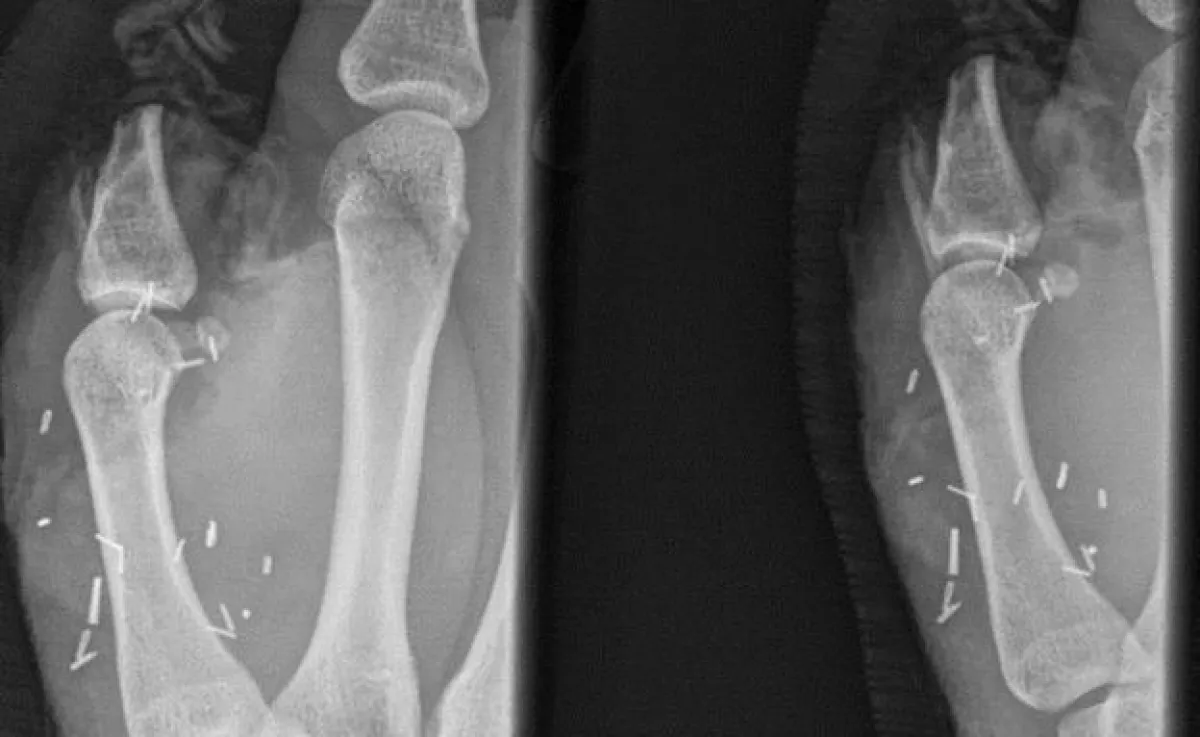

وكان الشاب زاك ميتشل قد أُصيب أثناء عمله في مزرعة نائية غربي أستراليا، عقب هجوم شرس من أحد الثيران عليه؛ مما تسبب له بقطع إصبعه الإبهام، بعد أن قام الثور بركل يد ميتشل في السور، وخضع الشاب الأسترالي قبل هذه العملية الغريبة، إلى عمليتين جراحيتين لم تنجحا في إعادة إلصاق إصبع الإبهام لديه؛ مما اضطر الأطباء إلى اللجوء لنقل إصبع قدمه الكبير ووضعه مكان الإبهام، في جراحة استغرقت قرابة ثماني الساعات، ورغم رفض الشاب في بداية الأمر لإجراء هذه العملية، إلا أنه وافق على إجرائها بمستشفى العيون في مدينة سيدني.

وقالت مستشفى العيون في سيدني، إنه من النادر زراعة إصبع قدم كامل كما في حالة ميتشل، لكن من الشائع إجراء جراحات لزرع أجزاء من أصابع القدم في أماكن أخرى.